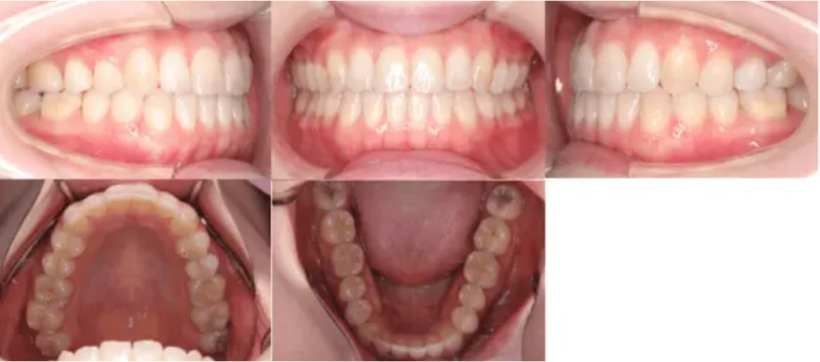

【治療後】

治療例②部分矯正: 23歳